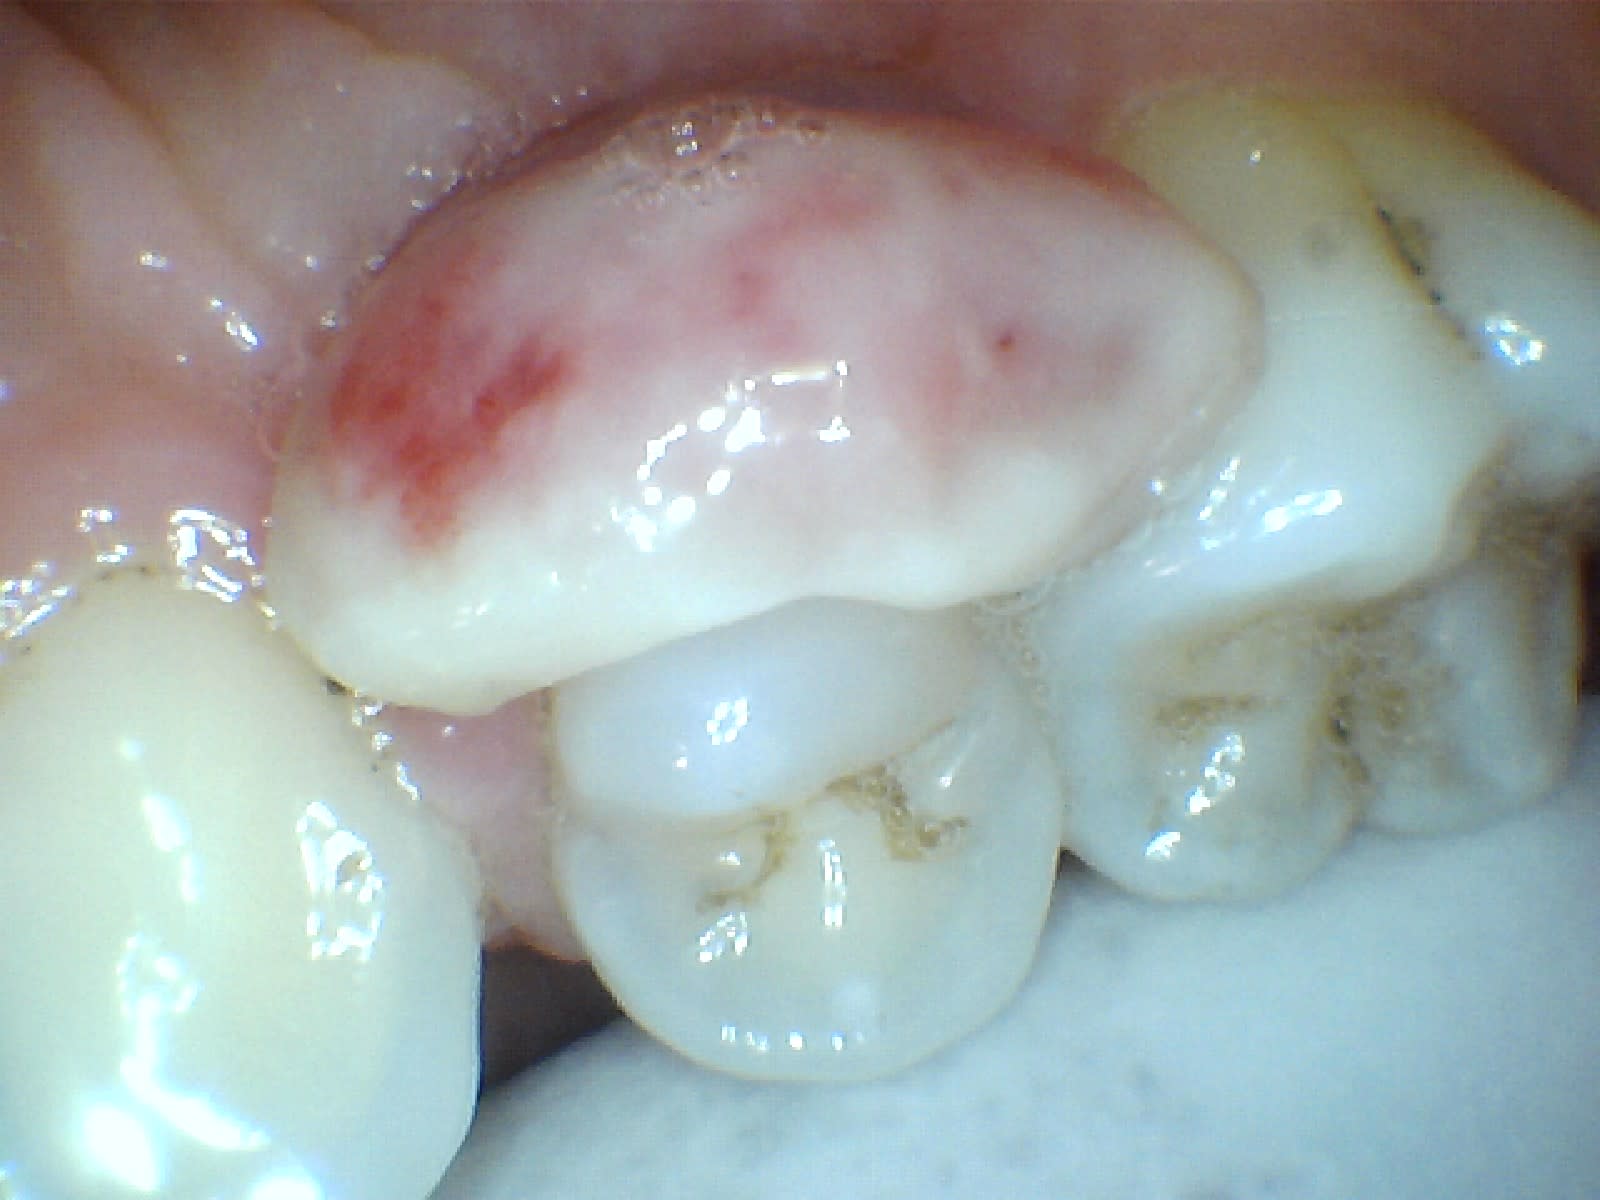

Patiente enceinte de 6 mois

Pas de douleur

bien pédiculé (au niveaudu collet), localisé en palatin de la 14

Je pars sur un epulis gravidique , je prefere poser la question ici par securité, comme j'ai pas l'habitude d'en voir